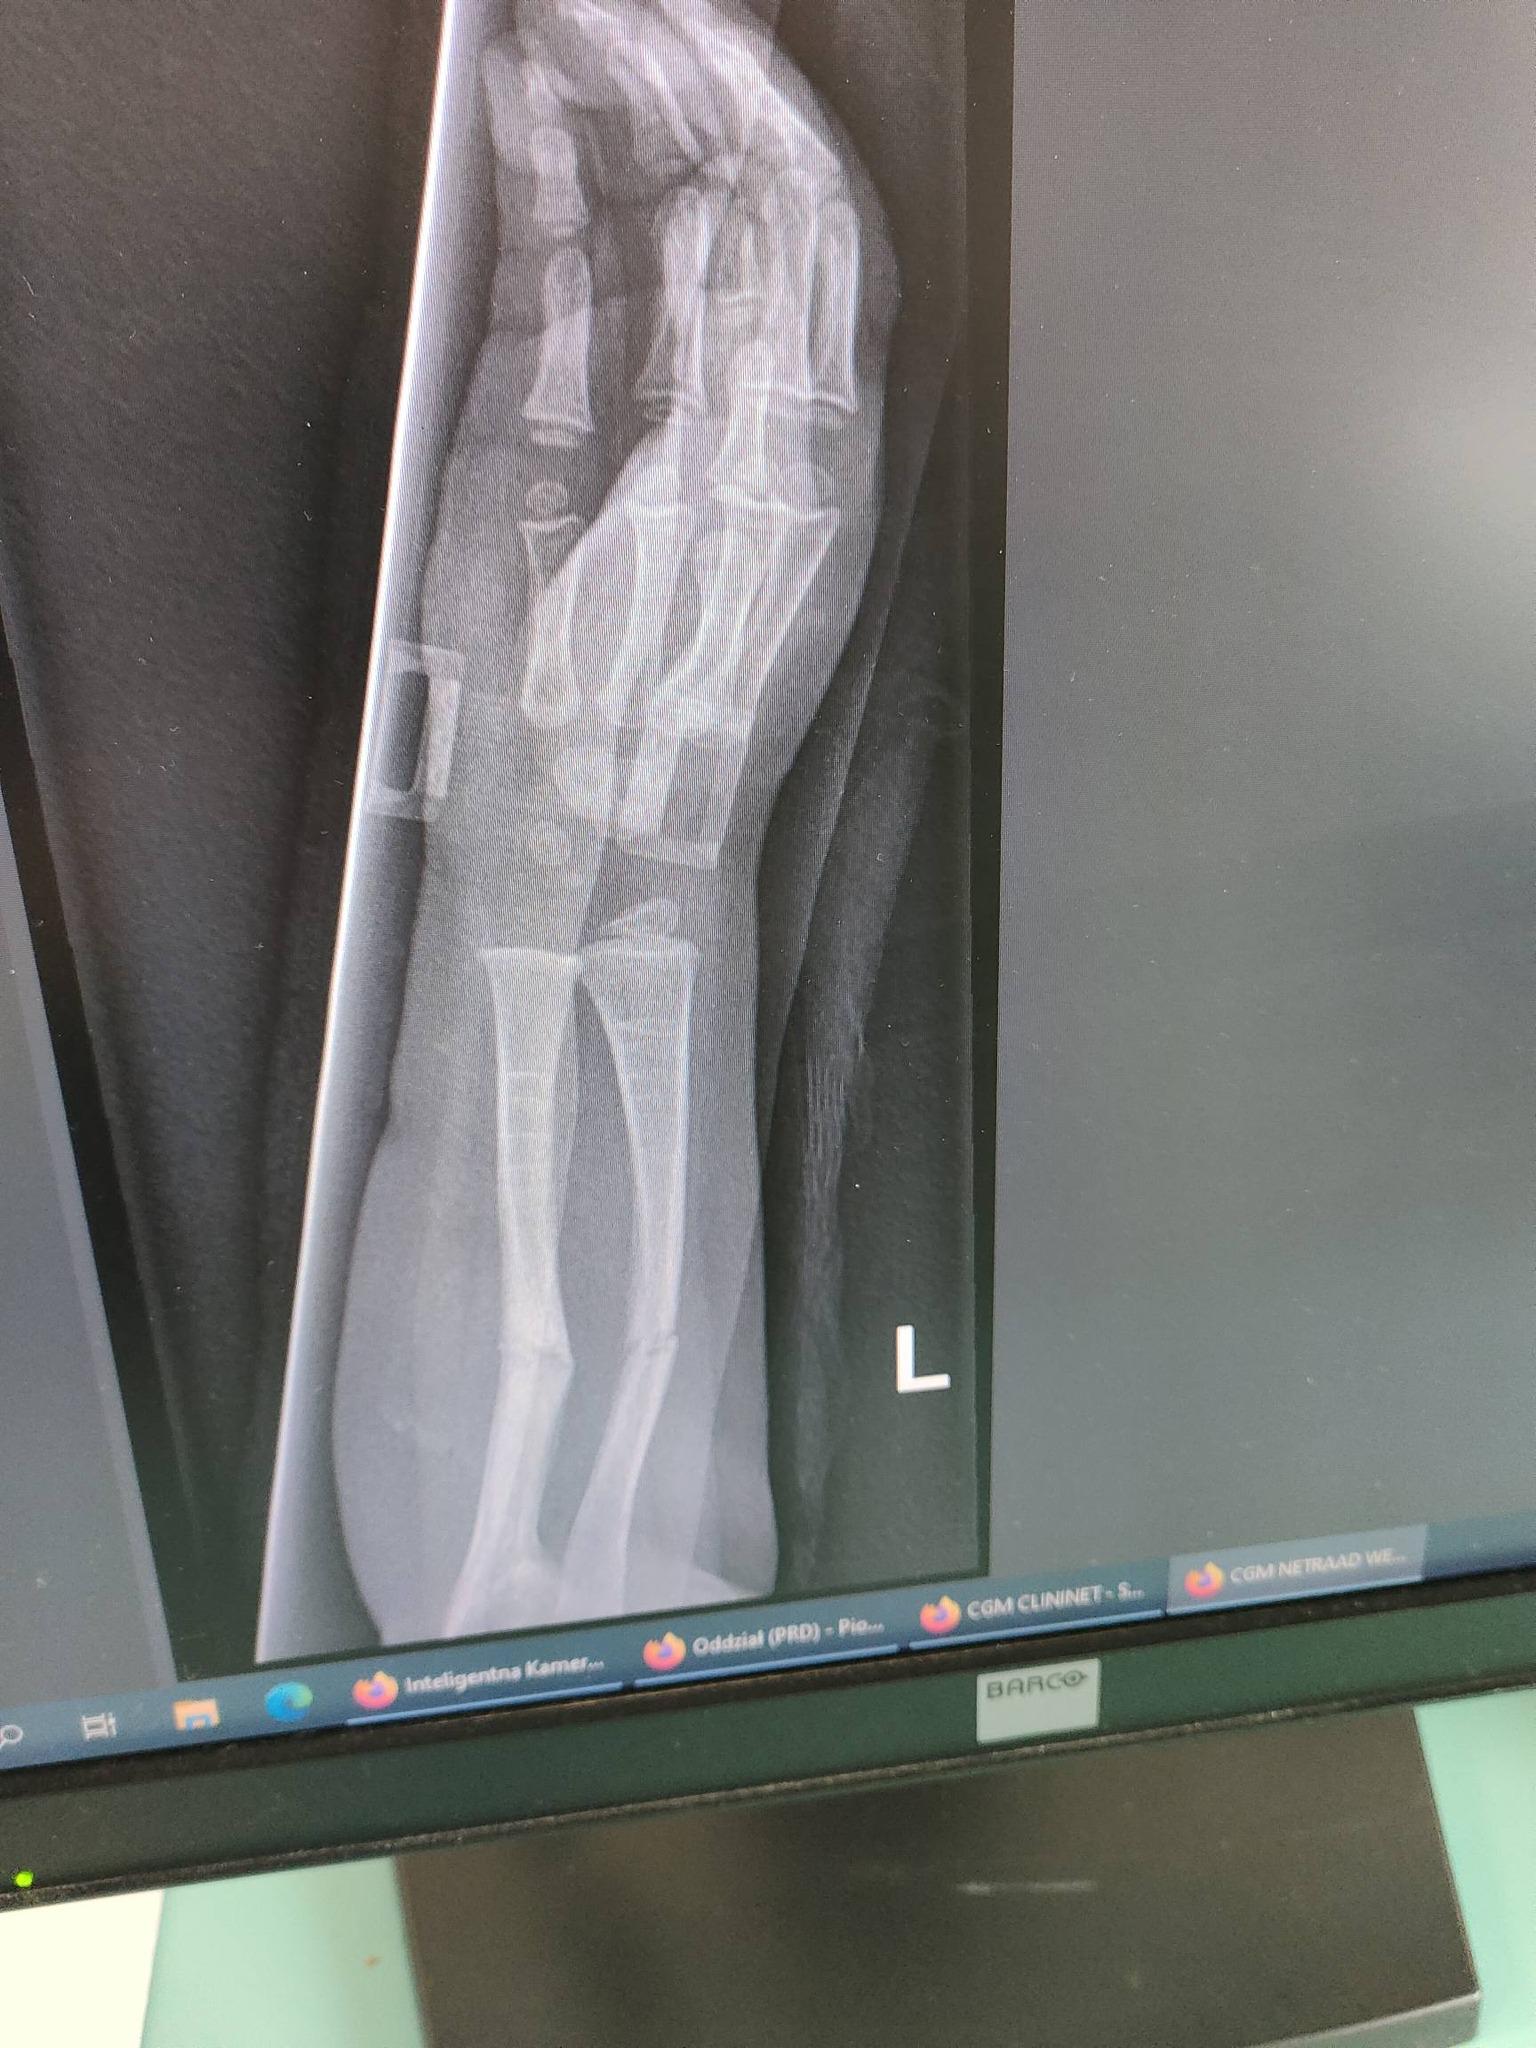

Madzia choruje na wrodzoną łamliwość kości typu III (osteogenesis imperfecta) – rzadką, genetyczną chorobę tkanki łącznej, która powoduje skrajną kruchość kości. Złamań doznała już w życiu płodowym, a jej organizm nie produkuje kolagenu. Choroba jest nieuleczalna, a leczenie ma charakter objawowy i obejmuje stałą rehabilitację, liczne operacje, stabilizację kości oraz specjalistyczną farmakoterapię. Dziewczynka ma za sobą już kilka poważnych zabiegów oraz kilkanaście podań leków wzmacniających kości. Przed nią kolejne operacje i intensywna fizjoterapia, bez której trudno byłoby myśleć o większej samodzielności.